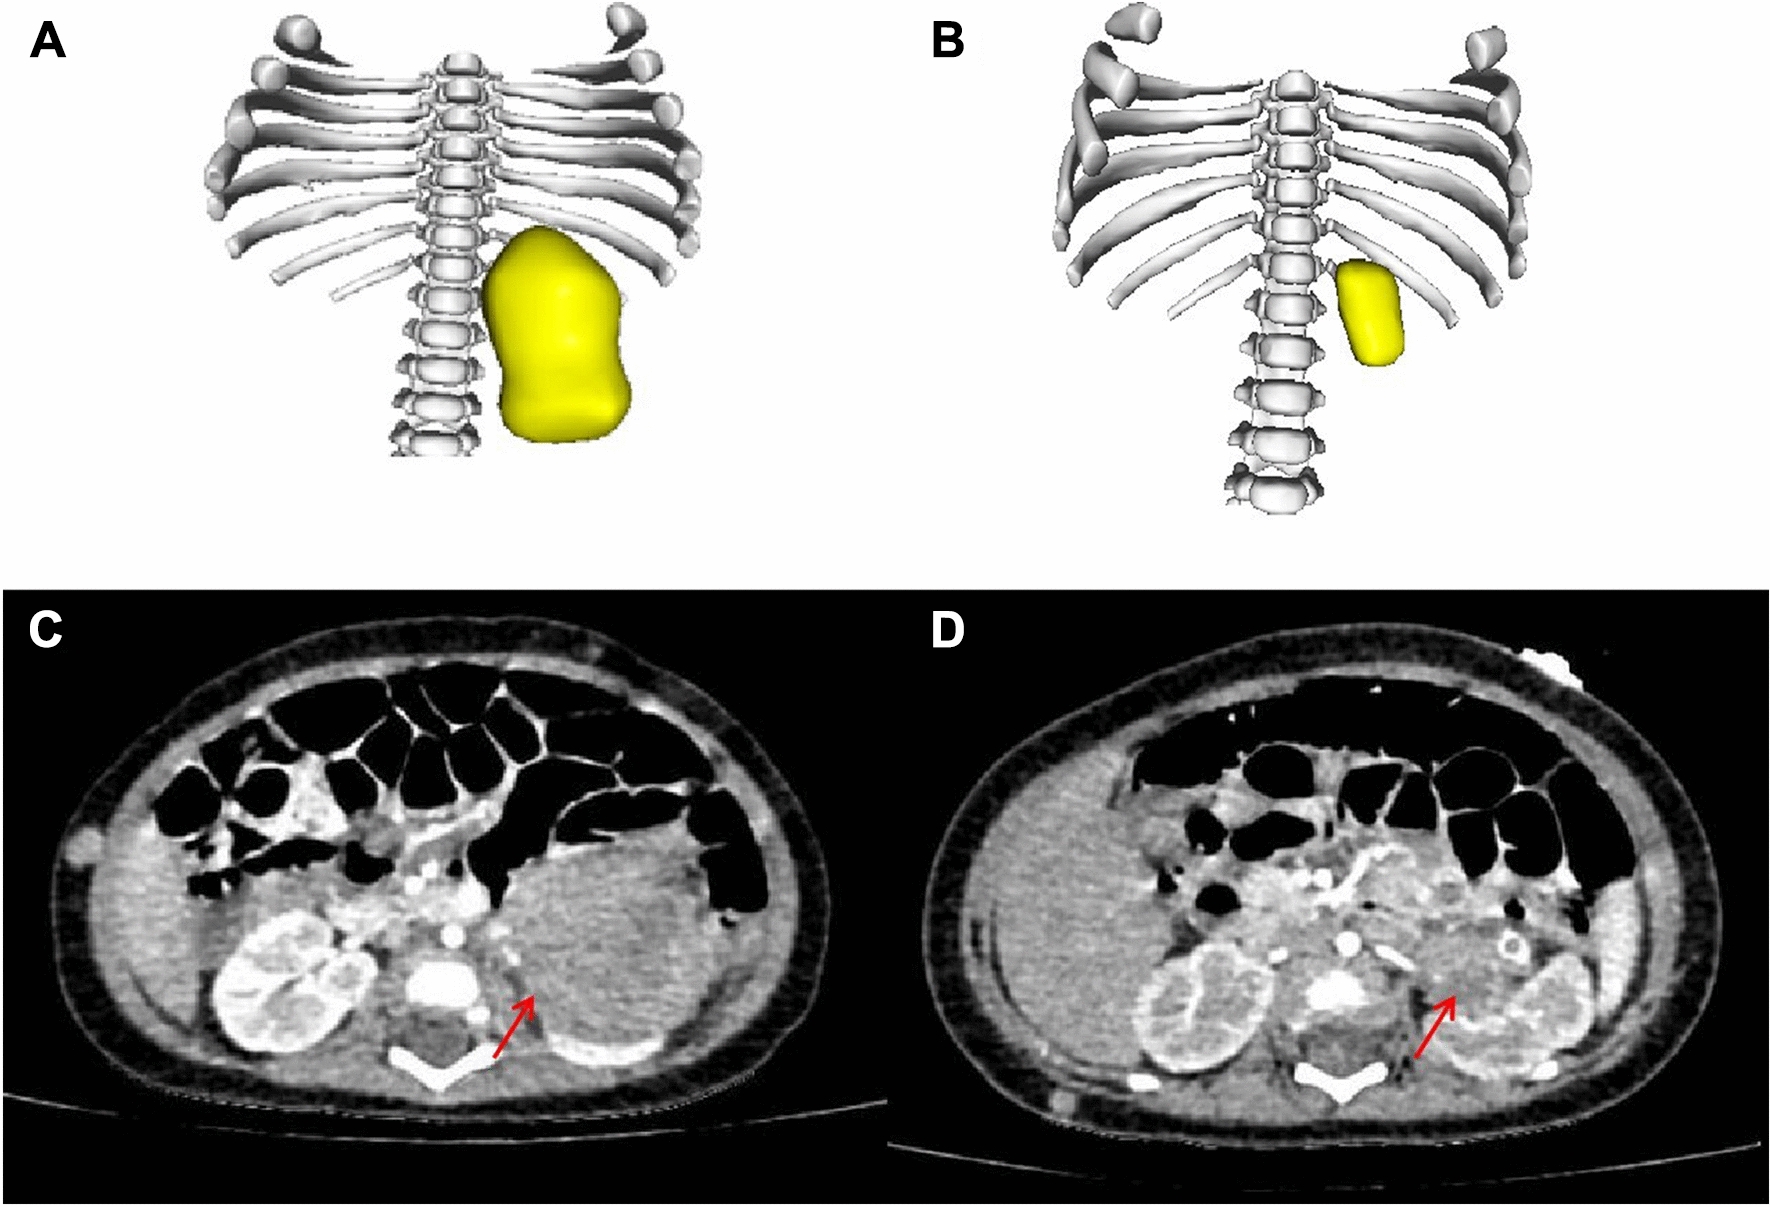

In terms of response evaluation, 5 patients had stable disease (SD), and 2 patients had partial remission (PR) according to the RECIST 1.1 standard. 3D tumor volume reconstruction was performed in 5 children before and after neoadjuvant chemotherapy (original image data from the initial enhanced CT examination were not available for 2 patients) [2]. The tumor volumes in all 5 children were significantly reduced, with a median volume reduction of 270 (IQR 83, 293) (range 49–413) ml; the most obvious reduction was from 55.7 to 6.6 ml (88.2%) (Table 3, Fig. 1). All 7 children received surgical treatment after neoadjuvant chemotherapy and received an additional 4–6 courses post-surgery.

Fig. 1.

Evaluation of response to neoadjuvant chemotherapy in one patient with ACC. A, B 3D reconstruction before (A) and after (B) neoadjuvant chemotherapy in a 4-month-old patient with stage IV ACC. C, D Enhanced CT before (C) and after (D) neoadjuvant chemotherapy. Location of the primary tumor focus (arrow)